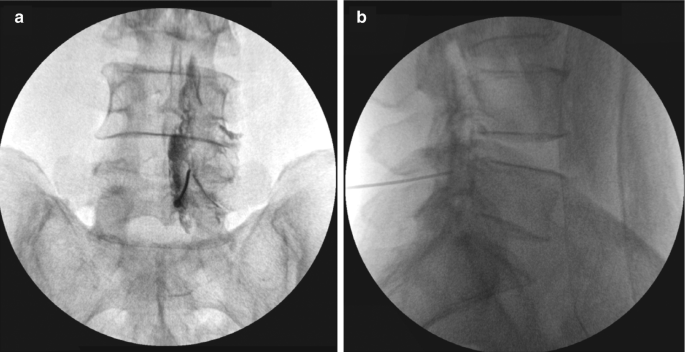

Interlaminar epidural injection

For the interlaminar route, patients were positioned prone on the procedure table with a pillow under the abdomen. The spinous processes of the lumbar vertebrae were palpated, and the specific interlaminar space for the injection was identified. After the area was cleaned and draped, 2% lignocaine (1 mL) was injected locally for anesthesia. Using an 18G or 20G spinal needle, the needle was inserted into the midline of the selected interlaminar space at a slight upward angle. The needle was advanced through the skin, subcutaneous tissue, supraspinous ligament, interspinous ligament, and ligamentum flavum until a loss of resistance was felt, indicating entry into the epidural space. Fluoroscopic guidance in AP and lateral views confirmed correct needle placement. A test dose of contrast dye was injected to ensure epidural placement and rule out intravascular or subarachnoid injection. The injection contained 4 mL of 2% xylocaine and 2 mL (80 mg) of methylprednisolone acetate (Fig. 3).

Figure 3: Needle positioning of interlaminar injection in anteroposterior view and lateral view.